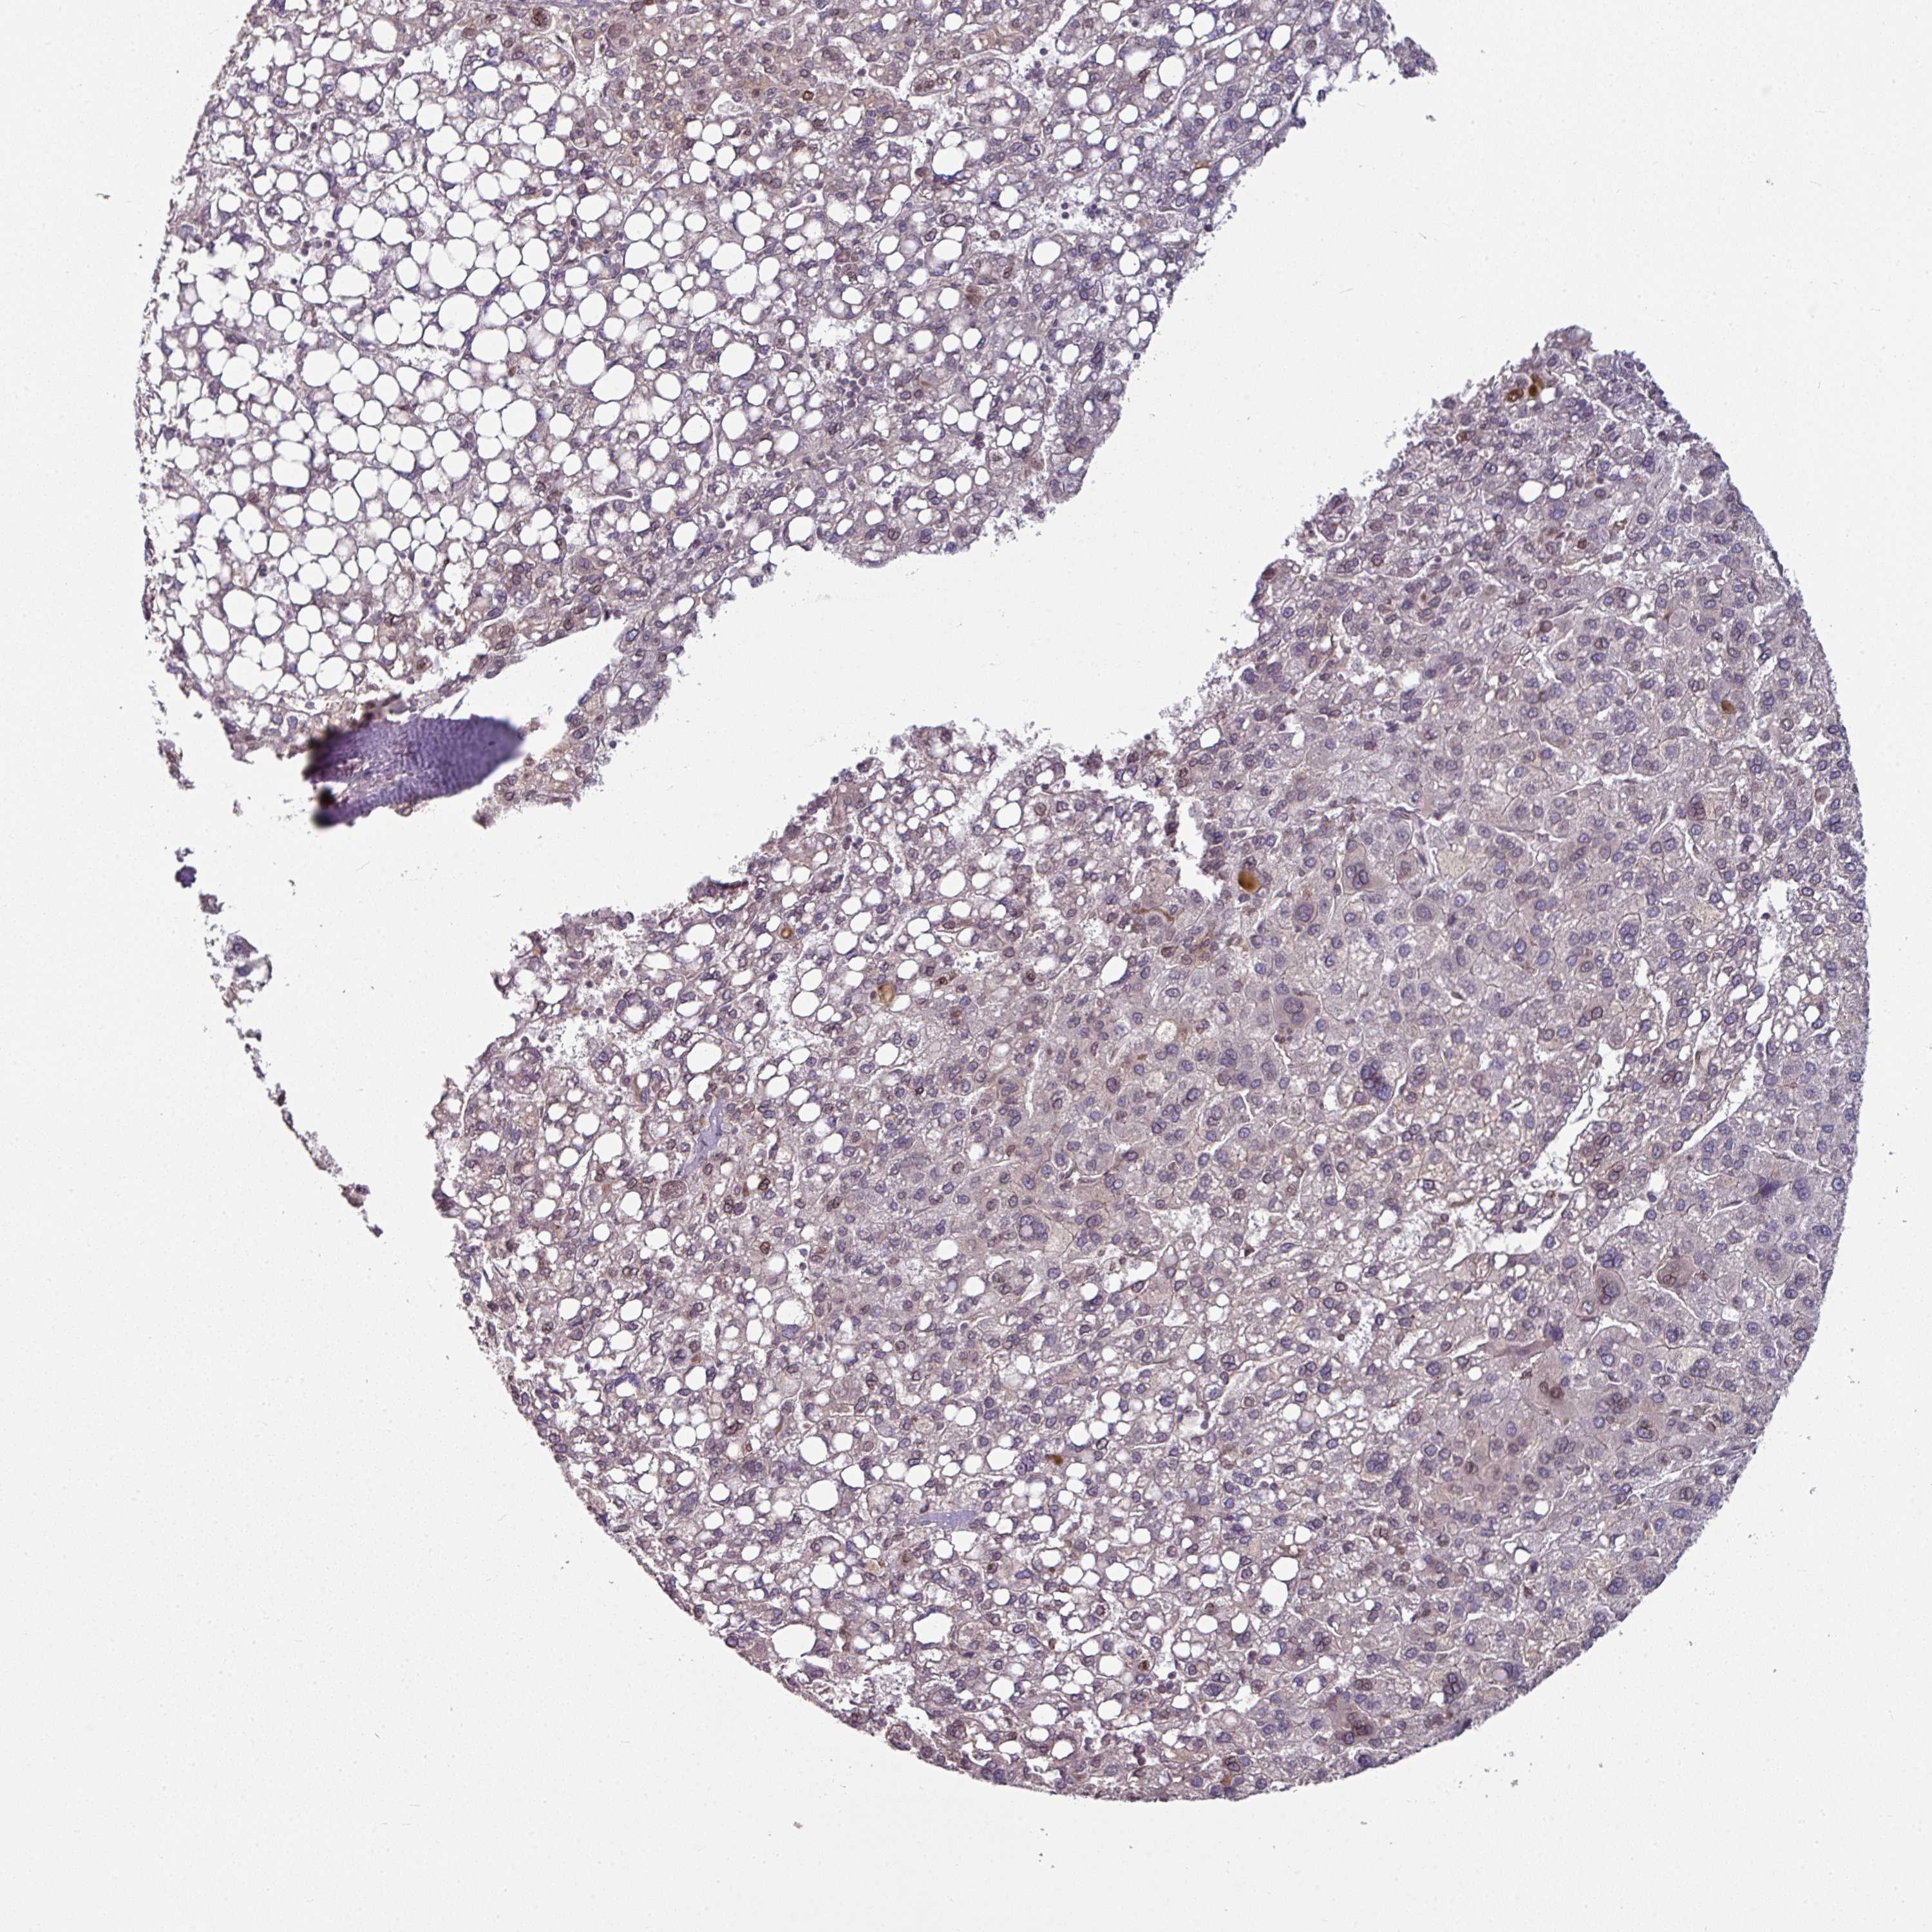

LIVER CANCER - Protein expressioni

A mouse-over function shows sample information and annotation data. Click on an image to view it in a full screen mode. Samples can be filtered based on level of antibody staining by selecting one or several of the following categories: high, medium, low and not detected. The assay and annotation is described here.

Note that samples used for immunohistochemistry by the Human Protein Atlas do not correspond to samples in the TCGA dataset.

Antibody stainingi

Antibody staining in the annotated cell types in the current human tissue is reported as not detected, low, medium, or high, based on conventional immunohistochemistry profiling in selected tissues. This score is based on the combination of the staining intensity and fraction of stained cells.

Each image is clickable and will lead to virtual microscopy that enables deeper exploration of all samples and also displays staining intensity scores, fraction scores and subcellular localization as well as patient and tissue information for each sample.

Antibody HPA050110

Antibody CAB004293

Staining

High

Medium

Low

Not detected

Intensity

Strong

Moderate

Weak

Negative

Quantity

>75%

75%-25%

<25%

None

Location

Nuclear

Cytoplasmic/membranous

Cytoplasmic/membranous,nuclear

Carcinoma, Hepatocellular, NOS

Cholangiocarcinoma